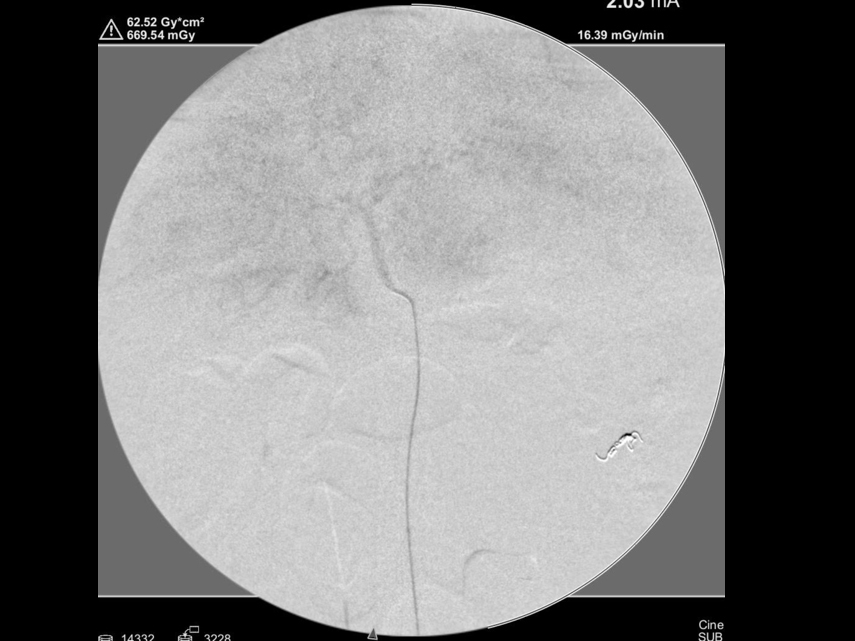

コイル塞栓後の造影検査(脾臓からの出血が止まったことを確認)

肝臓の造影検査を実施し肝臓からの出血がないことを確認